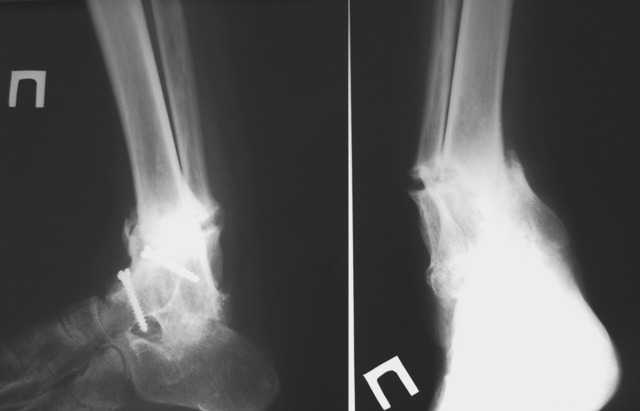

Уважаемые коллеги! Обращаюсь за советом. Пациентка, страдающая ревматоидным артритом, 2

года назад была оперирована по поводу вторичного деформирующего артроза голеностопного

сустава с варусной деформацией на этом уровне. В то время деформация была обусловлена

деструкцией тарана, поэтому был выполнен артродез по Кэмпбеллу. Спустя 2 месяца после

операции сформировался костный анкилоз голеностопа в физиологическом положении+анкилоз

задней фасетки подтарана, пациентка была в восторге, т.к. до этого намаялась со стоптанной

обувью, нарушенной походкой, с ортезами и, соответсвенно, с потертостями и

гиперкератозами. Тем не менее, нынче обращается с ТЕМИ ЖЕ ПРОБЛЕМАМИ, которые исподволь

нарастали в течение 1,5-2 месяцев. Делаем снимки и, о ужас, видим лоозеровскую зону выше

анкилоза, клинически тот-же варус. Ясно, что лоозера срастим как-нибудь, но, наверное,

надо-бы еще что-то сделать, дабы избежать повторов. PS. С пациенткой доверительные,

хорошие отношения.